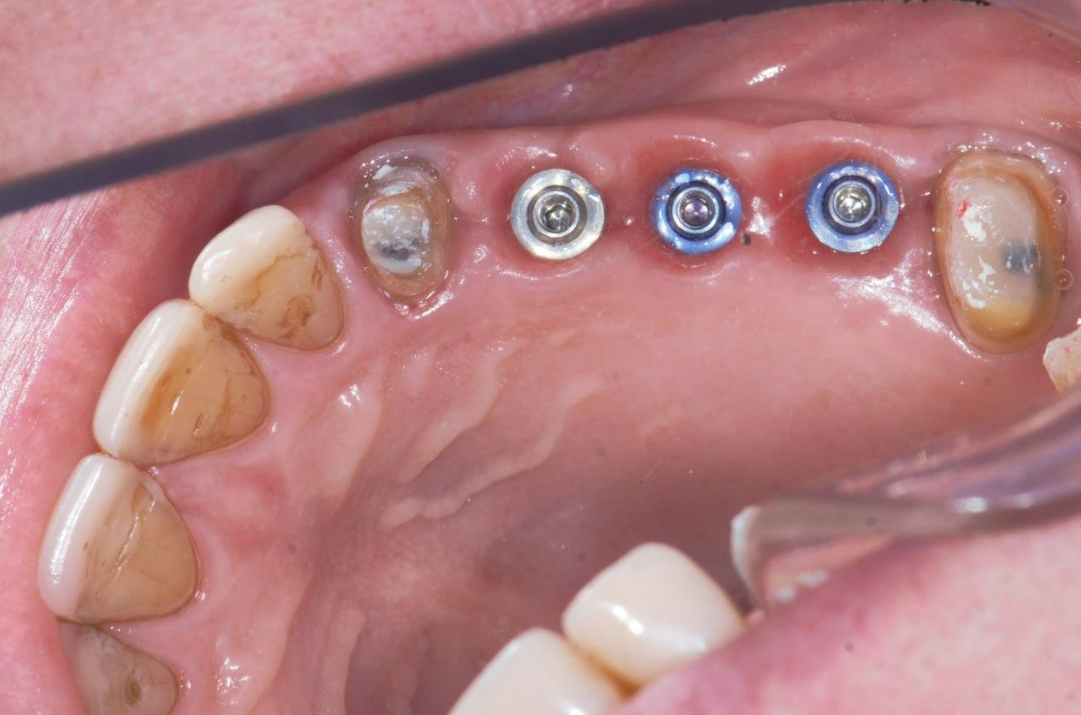

The illustration shows V-Type multi-unit abutments prior to the prosthetic stage: two abutments with a height of 2mm and one abutment with a height of 0.5mm.

| Tooth Position (FDI) | MUA Type & Gingival Height |

|---|---|

| #14 | V-Type MUA – 2 mm |

| #15 | V-Type MUA – 2 mm |

| #16 | V-Type MUA – 0.5 mm |

| Total: 3 Positions | 2× GH 2mm • 1× GH 0.5mm |